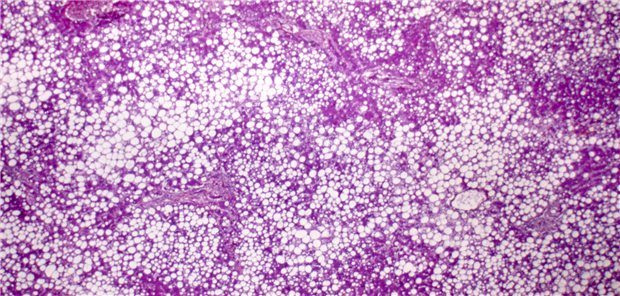

Xenotransplantation

Erstmals genetisch modifizierte Schweineleber in lebenden Menschen transplantiert